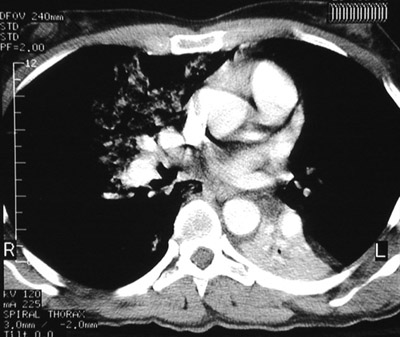

The scattered floccular bright areas are seen involving mainly the right upper lobe in this chest CT scan. There is also atelectasis of the left lower lobe from aspiration with bronchial obstruction.